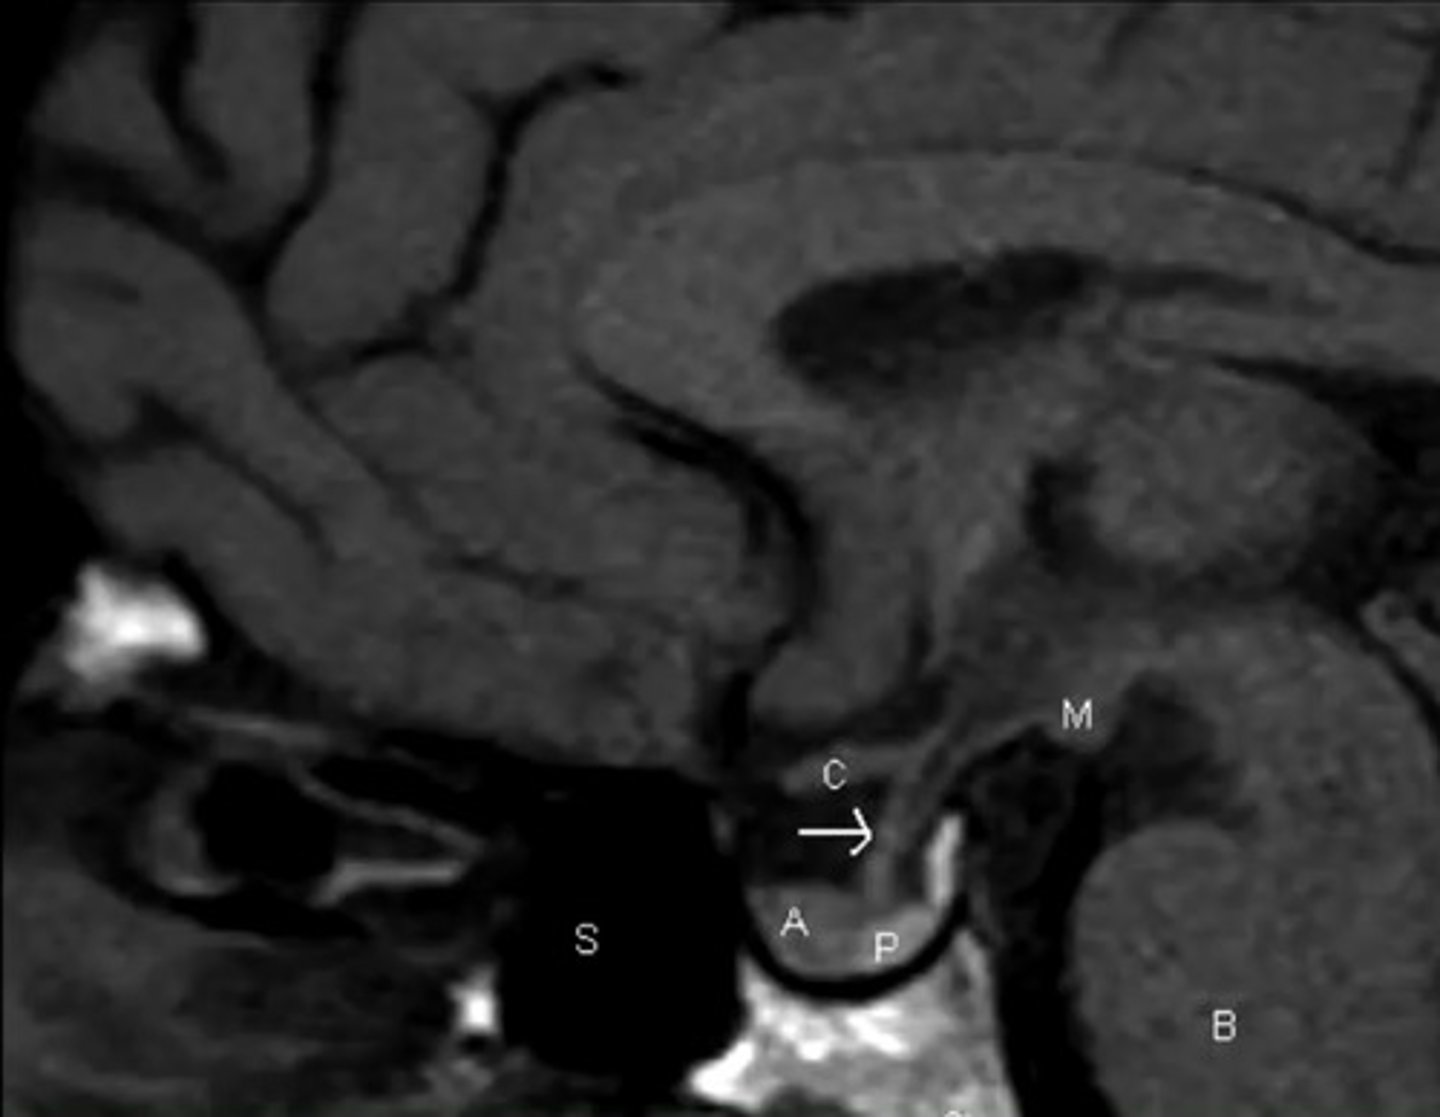

What is something to consider with MRI or CT when imaging for the pituitary?

You might have to order special testing, to get thin enough slices to catch smaller tumors